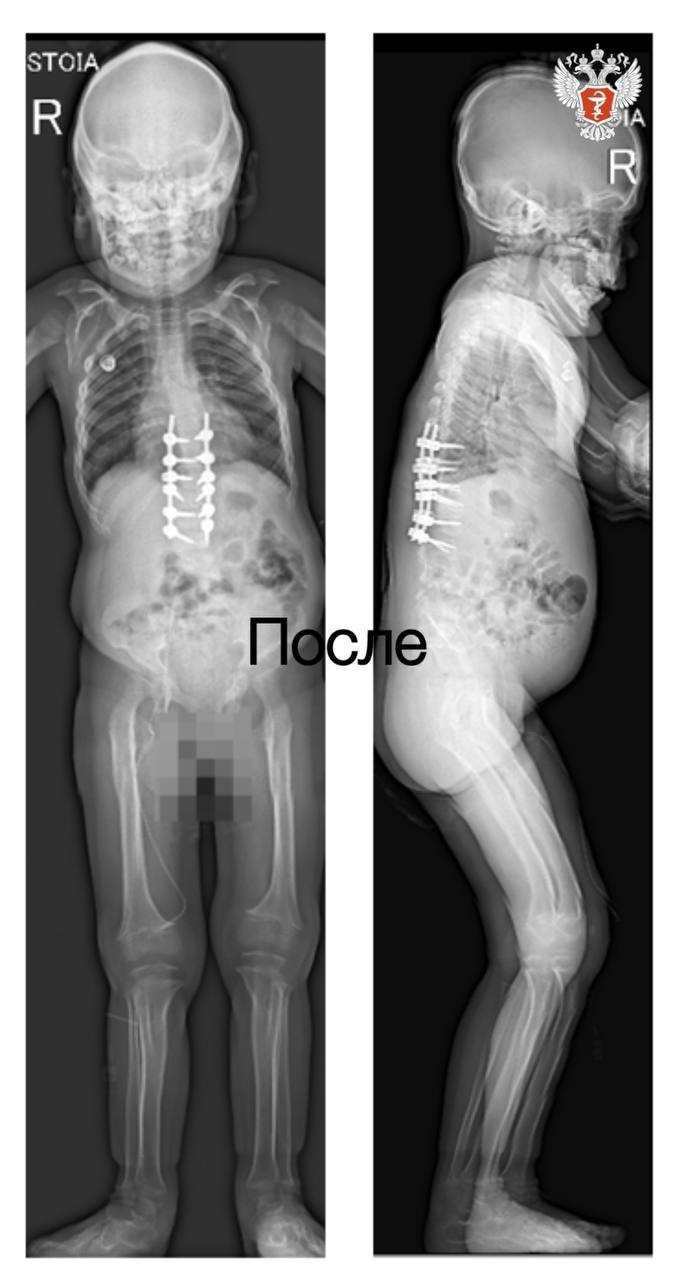

— В 2024 году мы исправили кифотическую деформацию, освободили спинной мозг и стабилизировали позвоночник. После этого у ребенка значительно улучшилась двигательная активность, — рассказала лечащий врач отделения №9 Клиники патологии позвоночника и редких заболеваний НМИЦ травматологии и ортопедии им. ак. Г.А. Илизарова Минздрава России Полина Очирова.

❤️ Операция прошла успешно. Сейчас девочка проходит курс реабилитации.